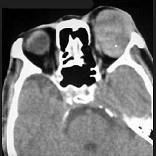

问题 男性45岁,左眼疼痛伴视力下降一个多月,左眼明显外突,CT扫描如图所示,最可能诊断为 ( )

选项 A、眶内结核 B、眶内转移瘤 C、眶内血管瘤 D、眶内纤维瘤 E、左侧眶内炎性假瘤

答案 E